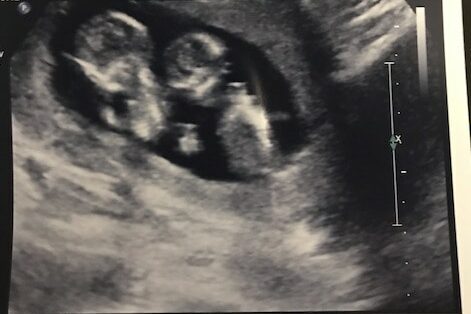

“At 10 weeks the ultrasound tech almost didn’t see our 2nd baby! She was nearly done with measurements and double-checking something when she suddenly announced that she was going to start over to be sure she was measuring the right baby each time! We were confused… for a moment and then shocked when she said there were two. It made me wonder how many times a twin isn’t known until much later.”

8 weeks, one baby and 12 weeks two babies

“I was 8 weeks along and went in for bleeding. Doctor said it was an SCH. At 12 weeks it turned out not to be SCH, but a 2nd baby”.

Twins can typically be detected on ultrasound during the first trimester, usually around 6 to 8 weeks of gestation. In some cases, healthcare providers may be able to identify the presence of twins even earlier, especially with advanced ultrasound technology. The ability to visualize twins on an ultrasound depends on factors such as the clarity of the image, the position of the embryos, and the experience of the ultrasound technician.